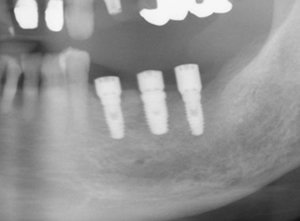

下のレントゲン写真はインプラント周囲炎になってしまった症例です。患者さんの希望によりインプラントリカバリーしました。

![]() |

現在骨も再生し、歯肉も安定しています。このあと被せ物の治療にはいります。